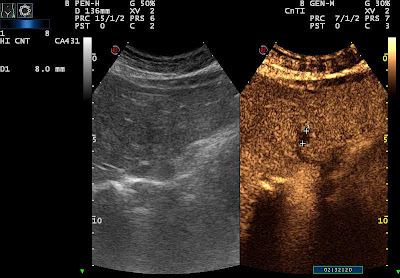

| fourth met |